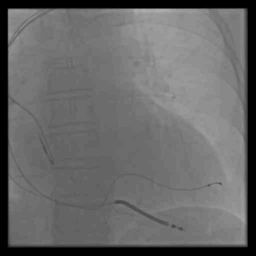

术前冠脉造影

血管选择 一

血管选择二

血管选择三

术中测试

● 左心室阈值:LV4-Coil 1.25V

● 右心室阈值:0.5V

● 右心房阈值:0.5V

最终影像